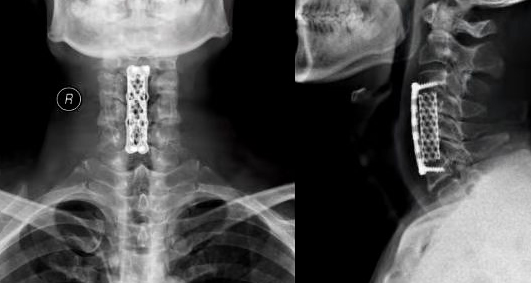

术后影像资料

接诊的脊柱外科主任医师王刚详细询问了杨先生的病史,并通过相关辅助检查诊断杨先生为脊髓型颈椎病。在了解杨先生的病症后,王刚同科室医护人员成功为杨先生实施了手术。手术历时2小时,术后第三天杨先生便开始了康复活动,整个人也精神了不少。术后的杨先生又露出了喜悦的笑容,值得开心的是以前抬不动腿的症状也消失了。杨先生表示,“我又能充满信心的大步向前了,为爱人和孩子创造一个温暖的家!”